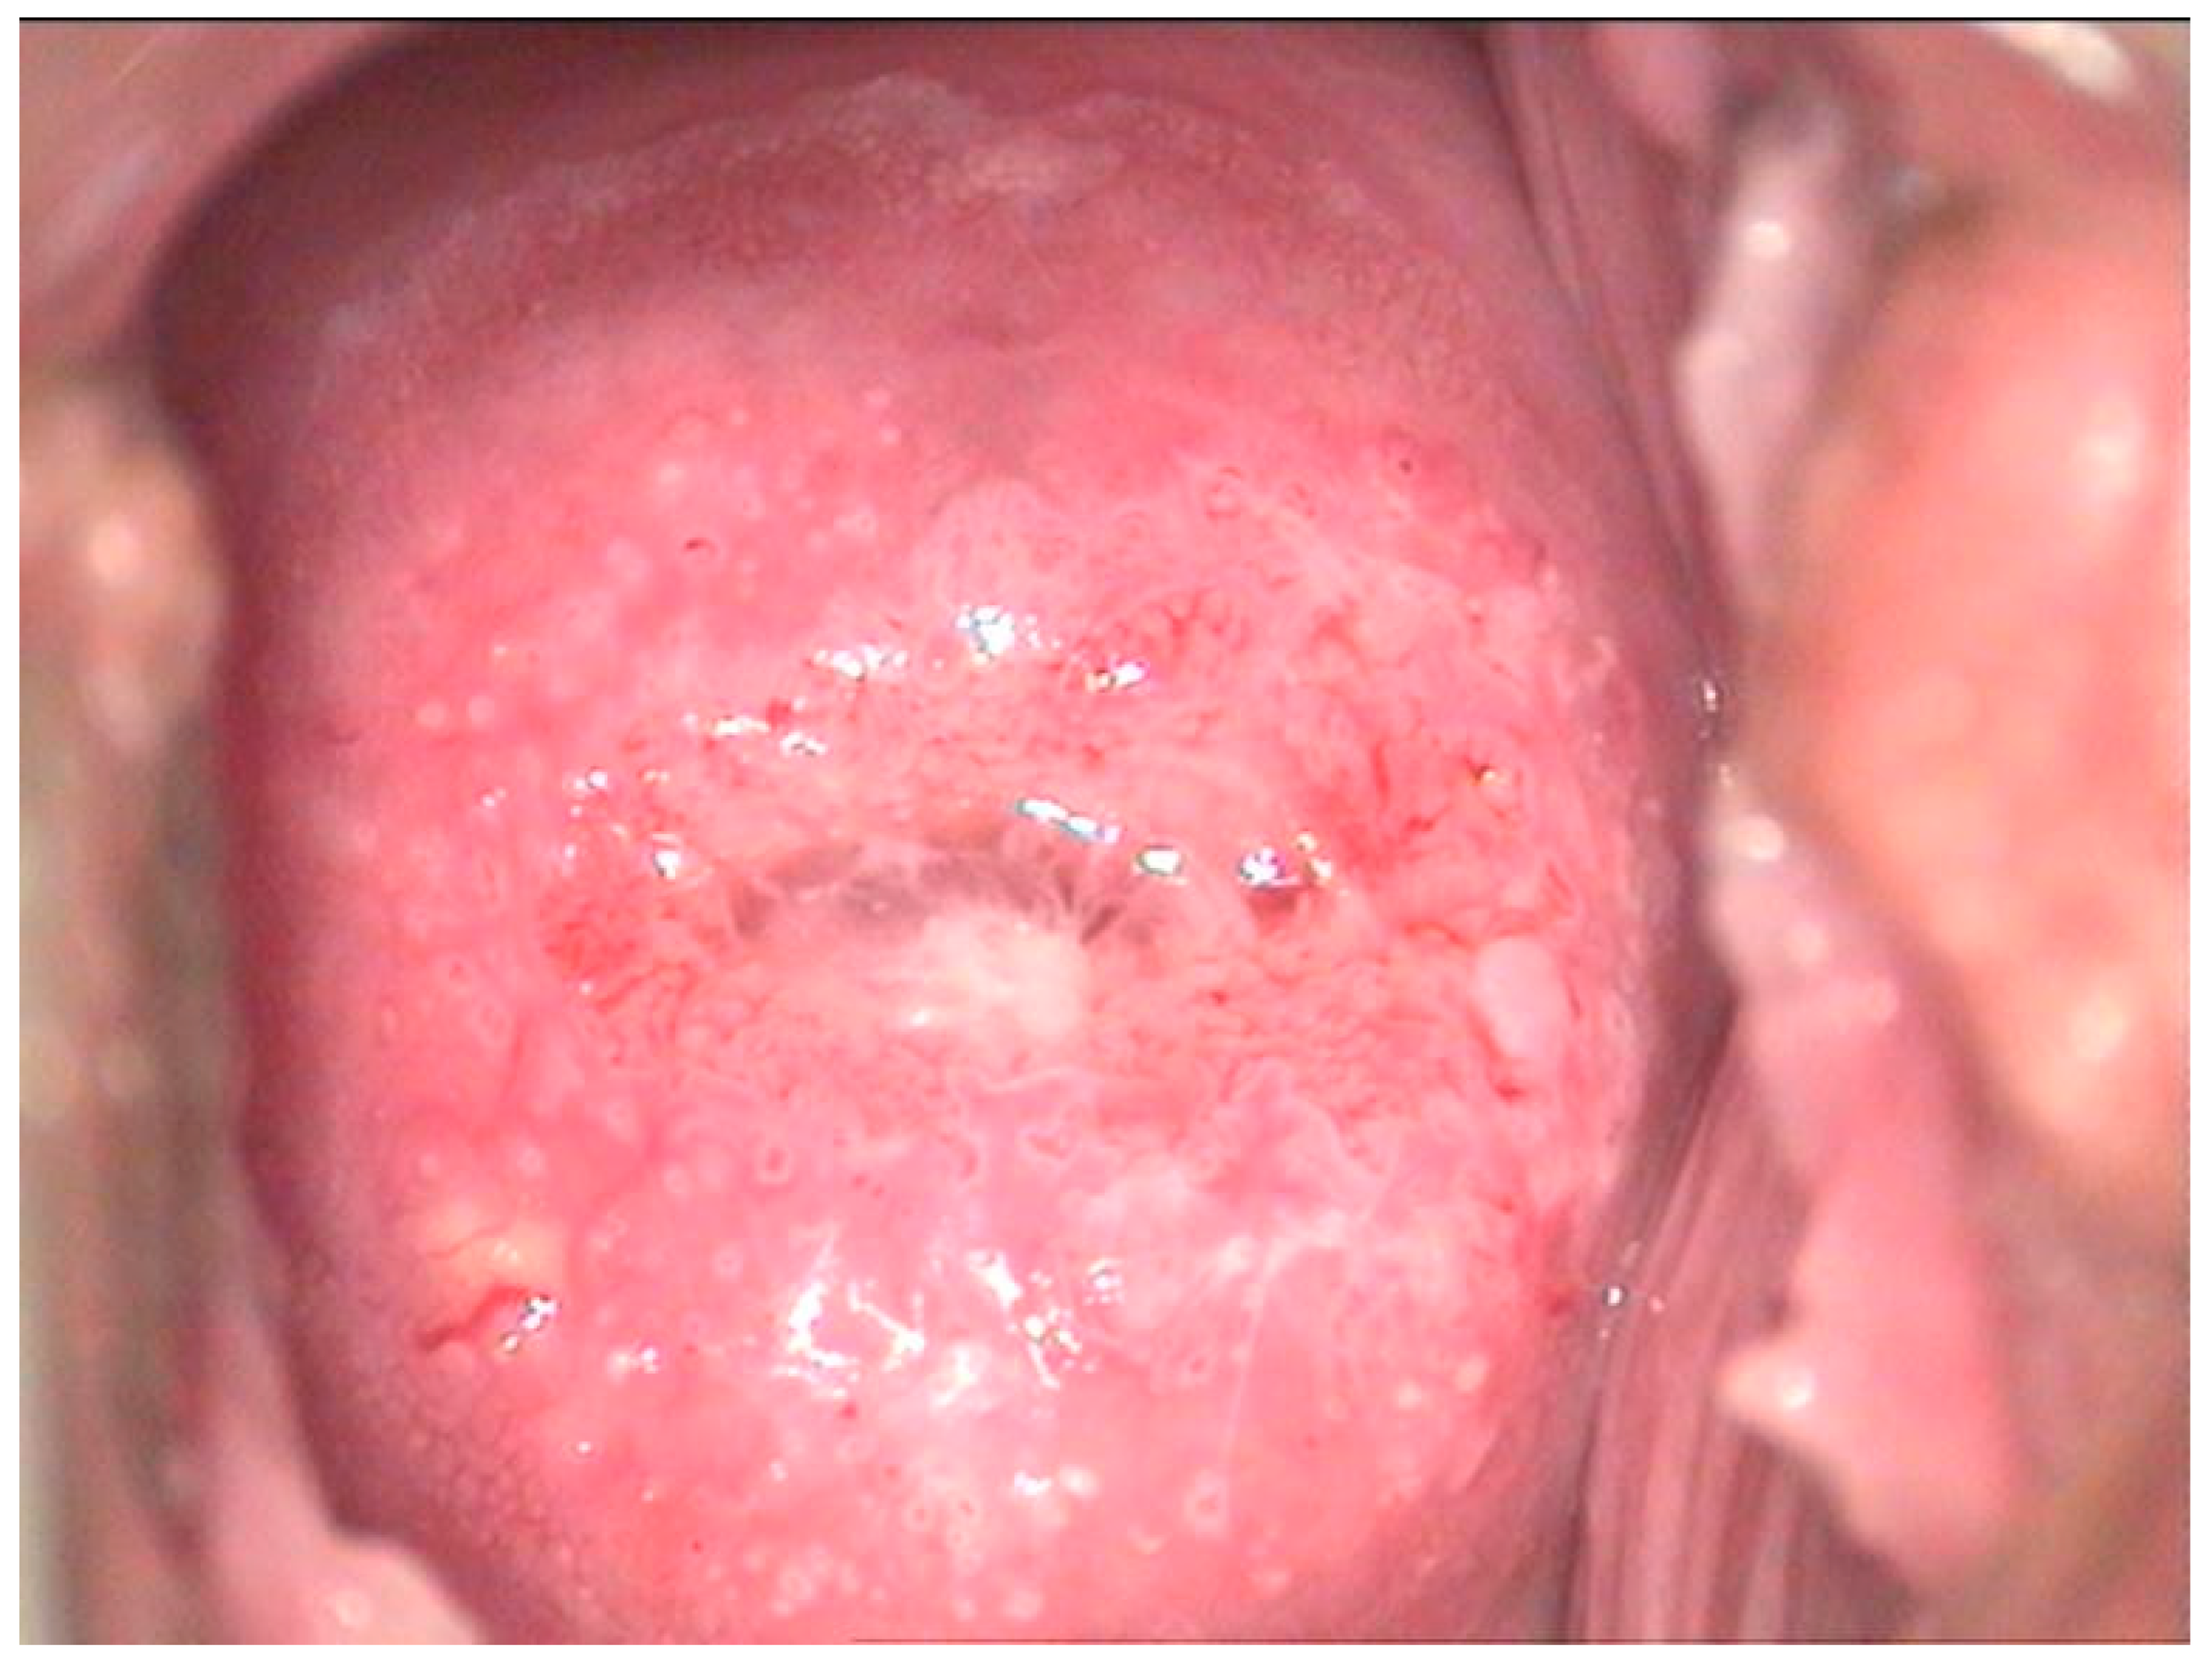

2.2. Clinical Examination